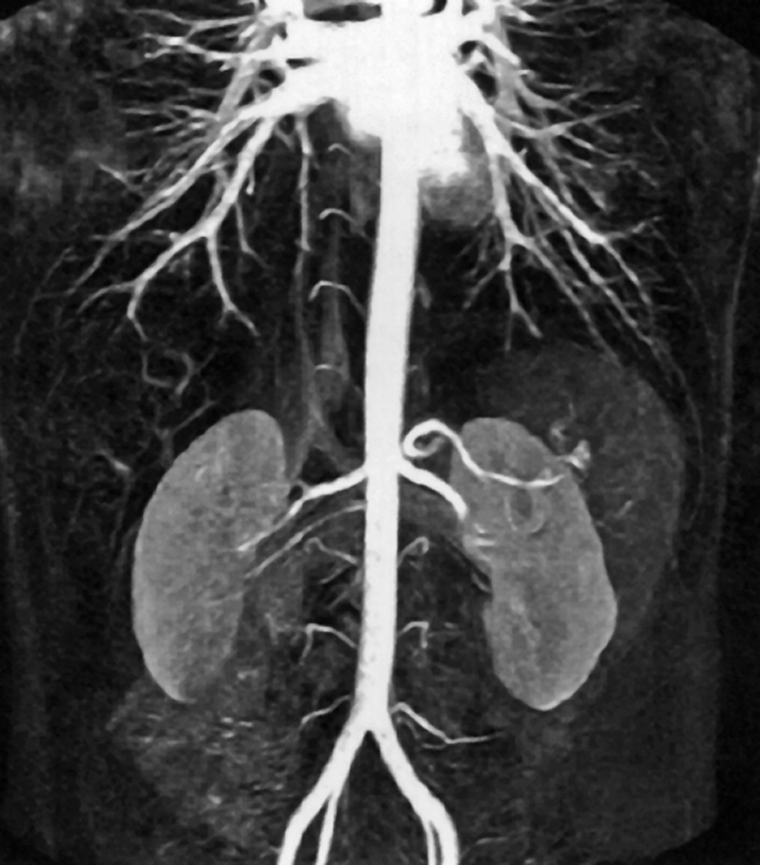

Figura 14-20:

CE-MRA of the abdominal aorta.

The distance of the arteries of interest to the heart, the cardiac output, and the qua­li­ty of the veins in which the agent is injected must also be taken into account (Fi­gu­res 14-20 and 14-21).